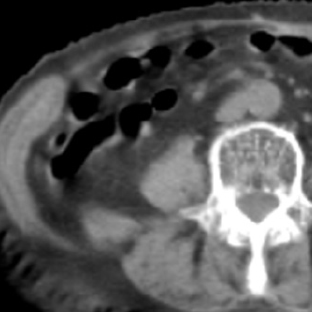

a. 123I-MIBG planar背面像

b. 単純CT

c. 123I-MIBG-SPECT/CT

図2 嚢胞変性した褐色細胞腫